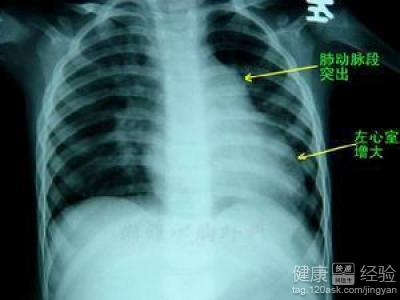

1右心衰竭第一個檢查就是去醫院做一個心髒的造影,看看右心房到底有多大才能夠判斷病情,才能夠對症治療。

2右心衰竭常常會連累肺部,這個時候我們應該排除肺部的病變,可以做一個血氣分析,看看肺部的功能好不好,才能夠對症治療。

3第三個需要做的檢查就是心電圖,心電圖可以排除左心衰竭的病症,這樣可以起到鑒別診斷的價值。